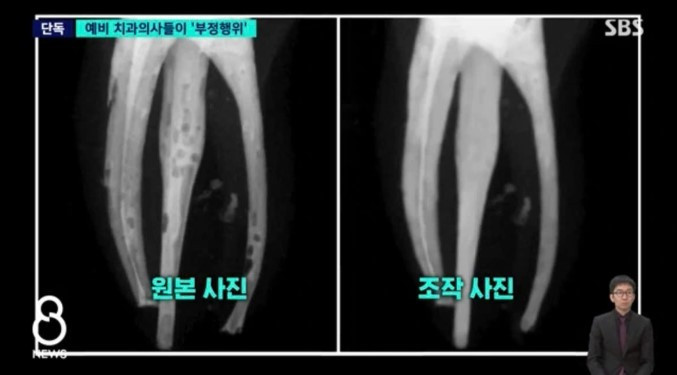

Theo kết quả rà soát, trong các phim X-quang chụp chân răng ở giai đoạn đầu, nhiều hình ảnh xuất hiện các điểm bất thường giống lỗ thủng. Qua phân tích chuyên môn, đây được xác định là các bọt khí hình thành do vật liệu trám không được lấp đầy hoàn toàn trong quá trình điều trị nội nha (điều trị tủy răng), phản ánh kết quả thực hành không đạt yêu cầu kỹ thuật.

Tuy nhiên, ở những hình ảnh cuối cùng được sinh viên nộp cho đội ngũ giảng viên, toàn bộ các khuyết điểm nói trên đã biến mất. Phim X-quang thể hiện kết quả điều trị gần như hoàn chỉnh, không còn dấu vết bọt khí, làm dấy lên nghi vấn về tính trung thực của dữ liệu thực hành.

Qua quá trình xác minh, nhà trường phát hiện các sinh viên đã sử dụng phần mềm Photoshop để can thiệp vào hình ảnh X-quang, khiến kết quả thực hành trông như đã được xử lý đúng quy trình kỹ thuật.